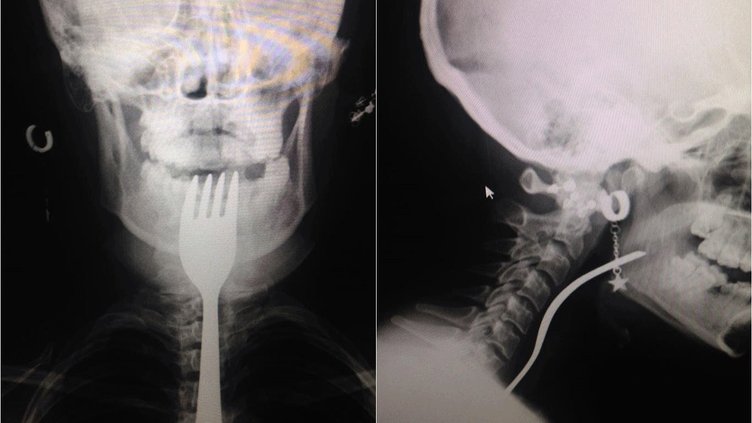

Aydın Söke'de yaşayan yabancı uyruklu E.E (18), yemek çatalı yuttuğu şikayetiyle ambulansla Aydın Adnan Menderes Üniversitesi (ADÜ) Hastanesine getirildi.

Burada röntgeni çekilen hastanın yemek borusunda 18 santimlik çatal olduğu tespit edildi.

Uzmanlar endoskopi yaparak çatalı ağızdan çıkarmayı denedi. Fakat yemek ve soluk borusuna zarar verme ihtimalinden dolayı midenin kesilerek çatalın çıkarılmasına karar verildi.

ADÜ Tıp Fakültesi Göğüs Cerrahisi Ana Bilim Dalı Öğretim Üyesi Dr. Salih Çokpınar ve Genel Cerrahi Ana Bilim Dalı Dr. Öğretim Üyesi Akay Edizsoy koordinasyonundaki operasyonla midede kesi açılarak çatal çıkarıldı.